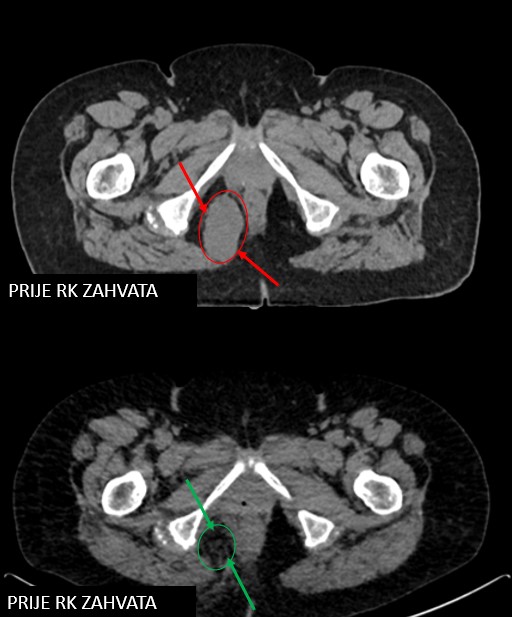

SABR meta fossae ischiorectalis (SB RCZ, 12.2.2019.)

Rezultat – 30 mjeseci nakon RK

Potpuni nestanak tretirane lezije